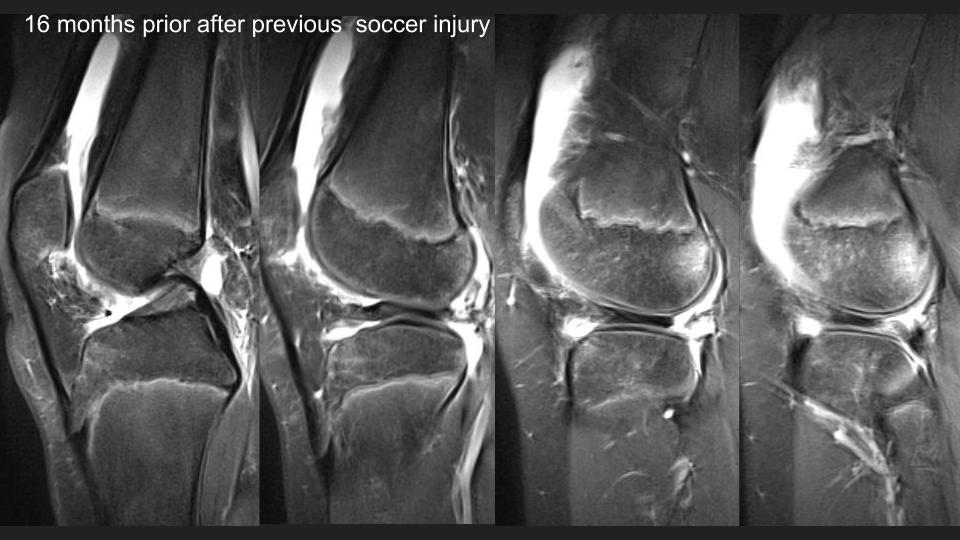

There is an anteriorly flipped bucket-handle type tear of a discoid lateral meniscus, which is not so interesting, until you see the prior MRI 16 months ago. At that time it appears that there was medial displacement of the posterior portion of the discoid LM, with thick irregular linear structures adjacent to the posterior horn region that I think were torn popliteomeniscal fascicles. Perhaps that predisposed to the current injury. The alternative possilbility is that this is a hypermobile discoid lateral meniscus, perhaps a Wrisberg variant. What do you think? Reference article.